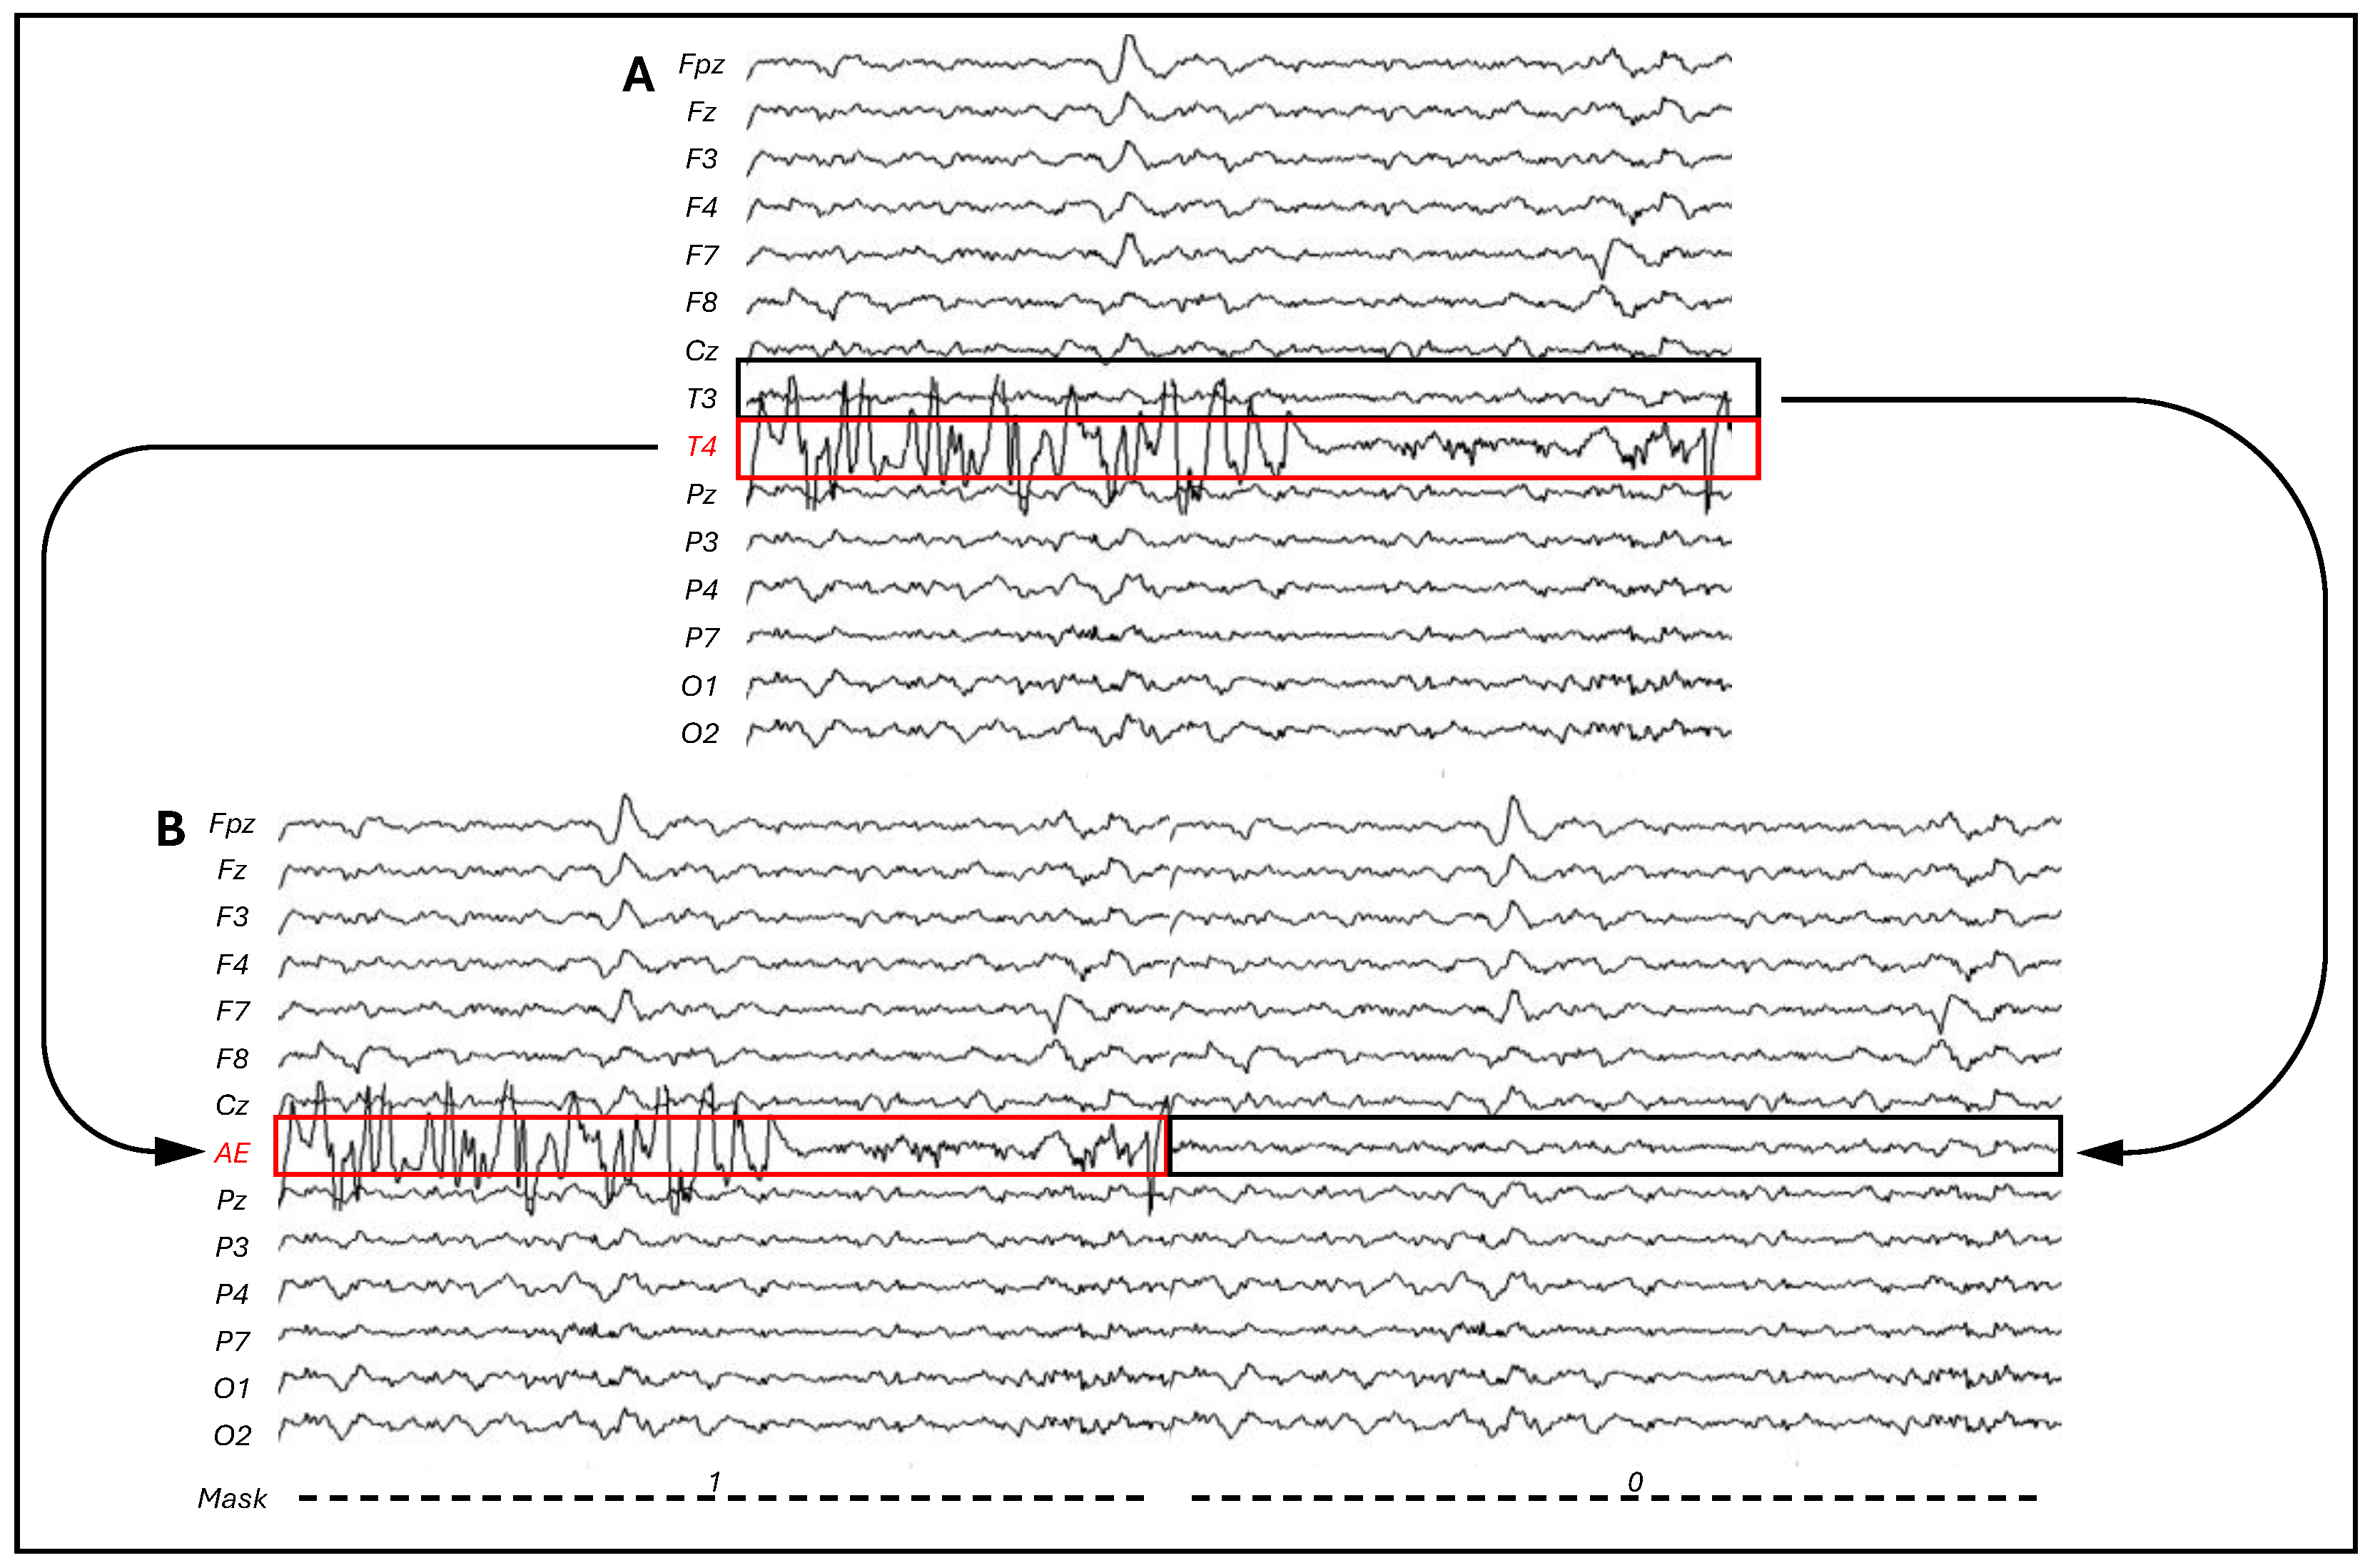

2.4. CI Artifact Removal

3.1. CI Artifact Characterization

3.2. CI Artifact Reduction